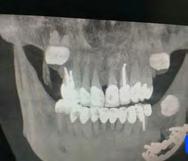

En la radiografía lateral de cráneo tenemos (Figura 7) la clase III esquelética con un ANB de -1, hiperdivergencia, aumento de la altura facial inferior, proclinación de los incisivos superiores con 1 a plano palatino de 133°, línea roja sobre la longitud del incisivo superior.

En la radiografía panorámica (Figura 8) se observan 32 dientes presentes

en boca, con la rehabilitación de los órganos dentarios por oclusal, con obturaciones de amalgamas, e incrustaciones, y divergencias radiculares inadecuadas.

Figura 7. Radiografía lateral de cráneo. Figura 8. Radiografía panorámica.

La radiografía lateral de cráneo en la Figura 11, se observa un ANB de 2° líneas rojas debido al avance del maxilar, una retroclinación del incisivo inferior a 76° líneas amarillas y mejoría de 1-maxilar a 122° líneas azules.

En la radiografía panorámica se ven 24 órganos dentales (Figura 12) después de realizada la cirugía osteotomía Lefort I maxilar de avance y una mentoplastía; las cuatro placas de fijación con sus respectivos microtornillos en el maxilar líneas de color rojo, la fijación con alambre quirúrgico de acero inoxidable señalados azules.